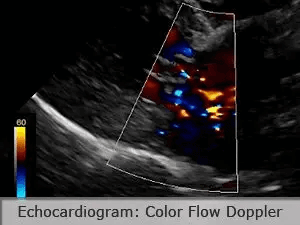

Cardiac Radiology (Xrays)Radiographs provide information on heart size, shape, and position. Abnormalities indicate specific changes within the heart due to heart disease. Radiographs also allow visualization of the lungs and indicate whether fluid is backing up from the heart into the lungs due to heart failure. The high def images captured with our equipment allow visualization of more subtle or early changes than low def images captured on standard radiology equipment. Echocardiography (Ultrasound of the heart)Echocardiography is a non-invasive specialized ultrasound imaging technique which allows visualization of the heart including the walls, chambers, and valves.

The following echocardiogram performed by Dr Stuart Ryder shows an abnormally thickened mitral valve. Color flow doppler demonstrates abnormal blood flow through the valve from the left ventricle backward into the left atrium. This dog’s abnormal measurements on radiographs (VHS) and echocardiogram (LA/AO ratio, LVIDDN) indicated it was a good candidate to start pre-symptomatic treatment with pimobendin. |